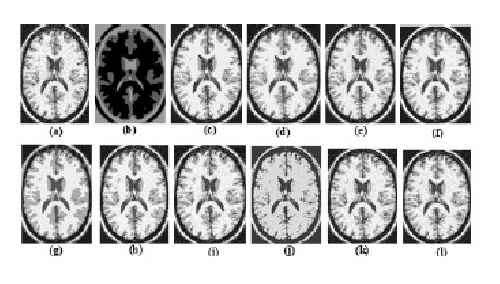

ترجمه مقاله تحلیل کارایی روش دسته بندی فازی C-Means برای قطعه بندی عکسهای MRI